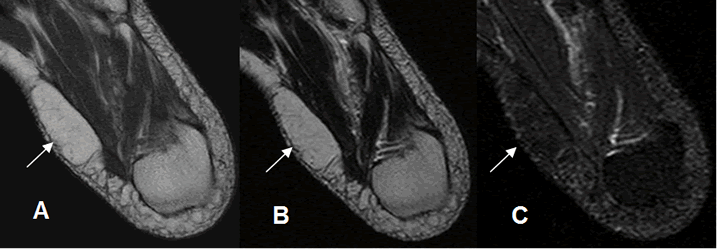

A: RM axial en T1, B: RM axial en T2 y C: RM axial en STIR. Lesión ovalada y encapsulada en la parte interna del pie, hiperintensa en T1 y T2 y que suprime en STIR, que corresponde a lipoma.